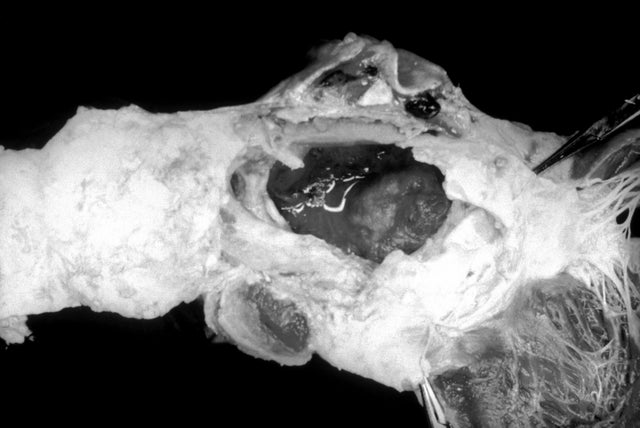

39. Aortic aneurysm and ripping

This image from 1971 shows a ruptured aortic aneurysm due to syphilis.